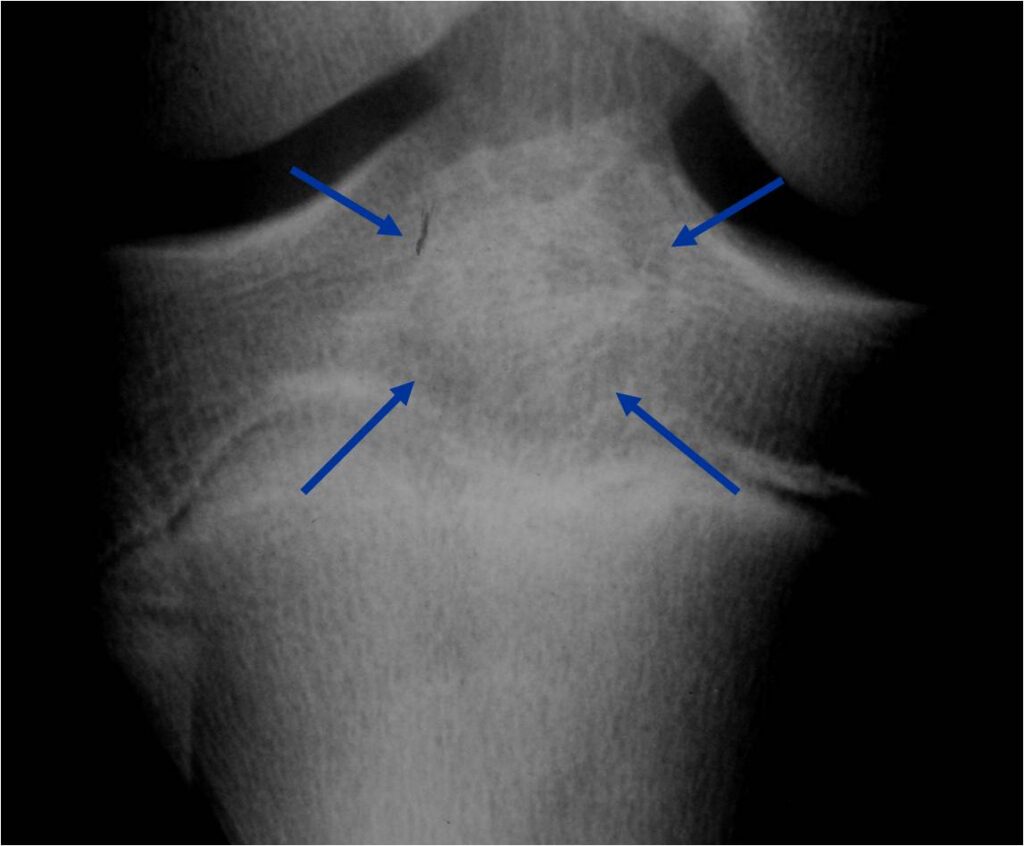

General Information Enchondroma is a benign indolent intramedullary hyaline cartilage neoplasm Accounts for 10% of all benign osseous tumors Limited growth, most lesions are less than 5 cm in maximal dimension Bones grow from a cartilaginous growth plate that...